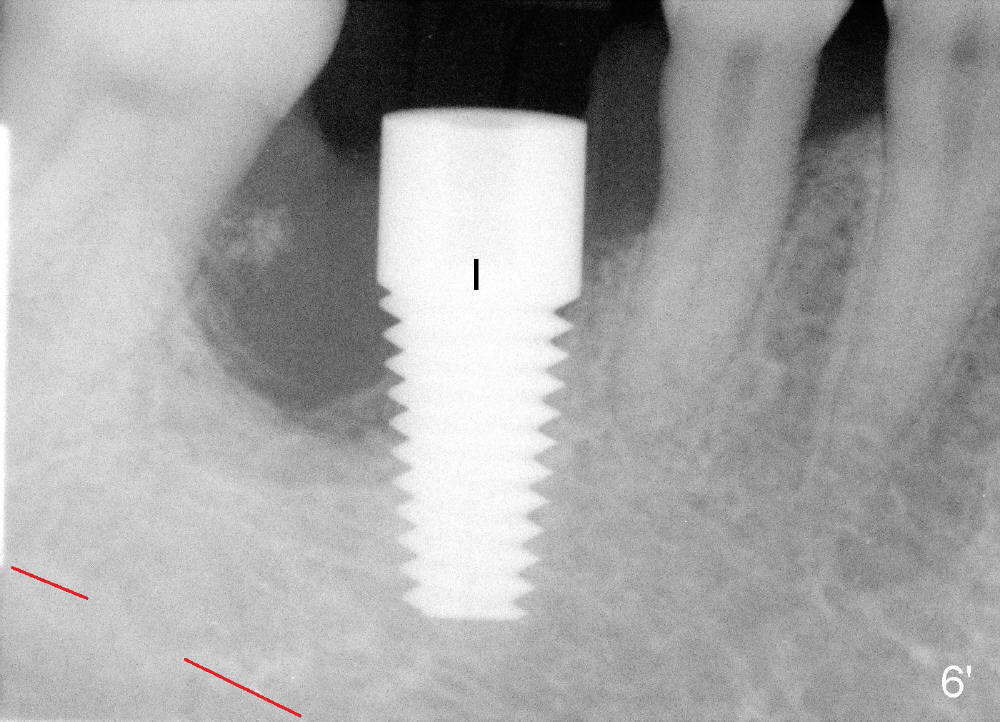

Finally, 7x17 mm implant is placed (Fig.6,6'). It appears that there is no bone contacting the top 3 threads of the implant distally (*). No bone graft is placed at the time of implant placement. It is thought that the existing infection may cause graft failure. With attention paid to eradicating socket infection (pre-, intra- and post-op antibiotic and removing granulation tissue after extraction), bone graft can be placed safely at the time of immediate implant.